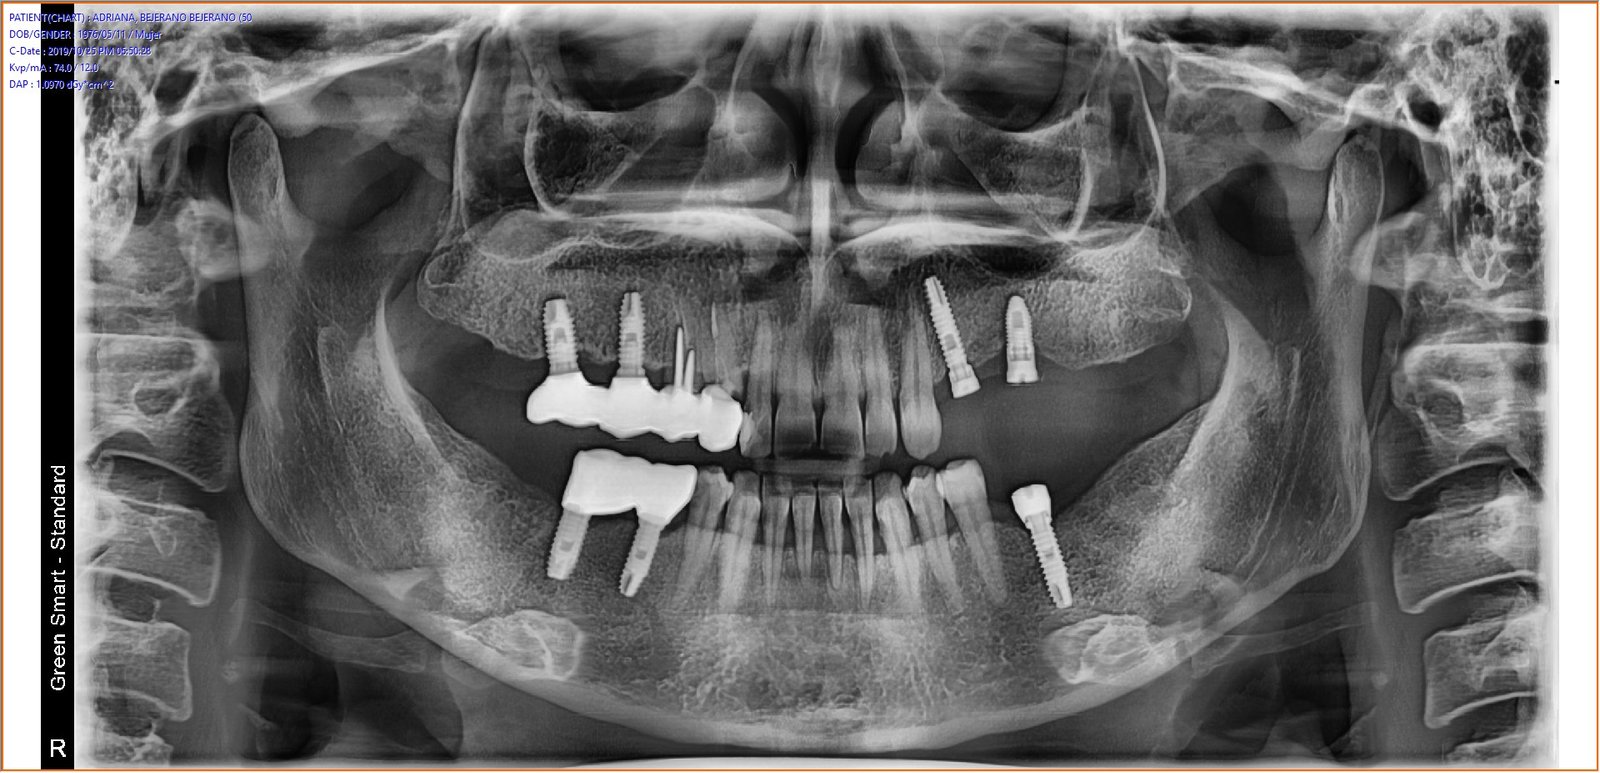

Buenas tardes, Necesitamos averiguar la marca de los Implantes superiores. Muchas gracias. Un saludo.

gracias de antemano!